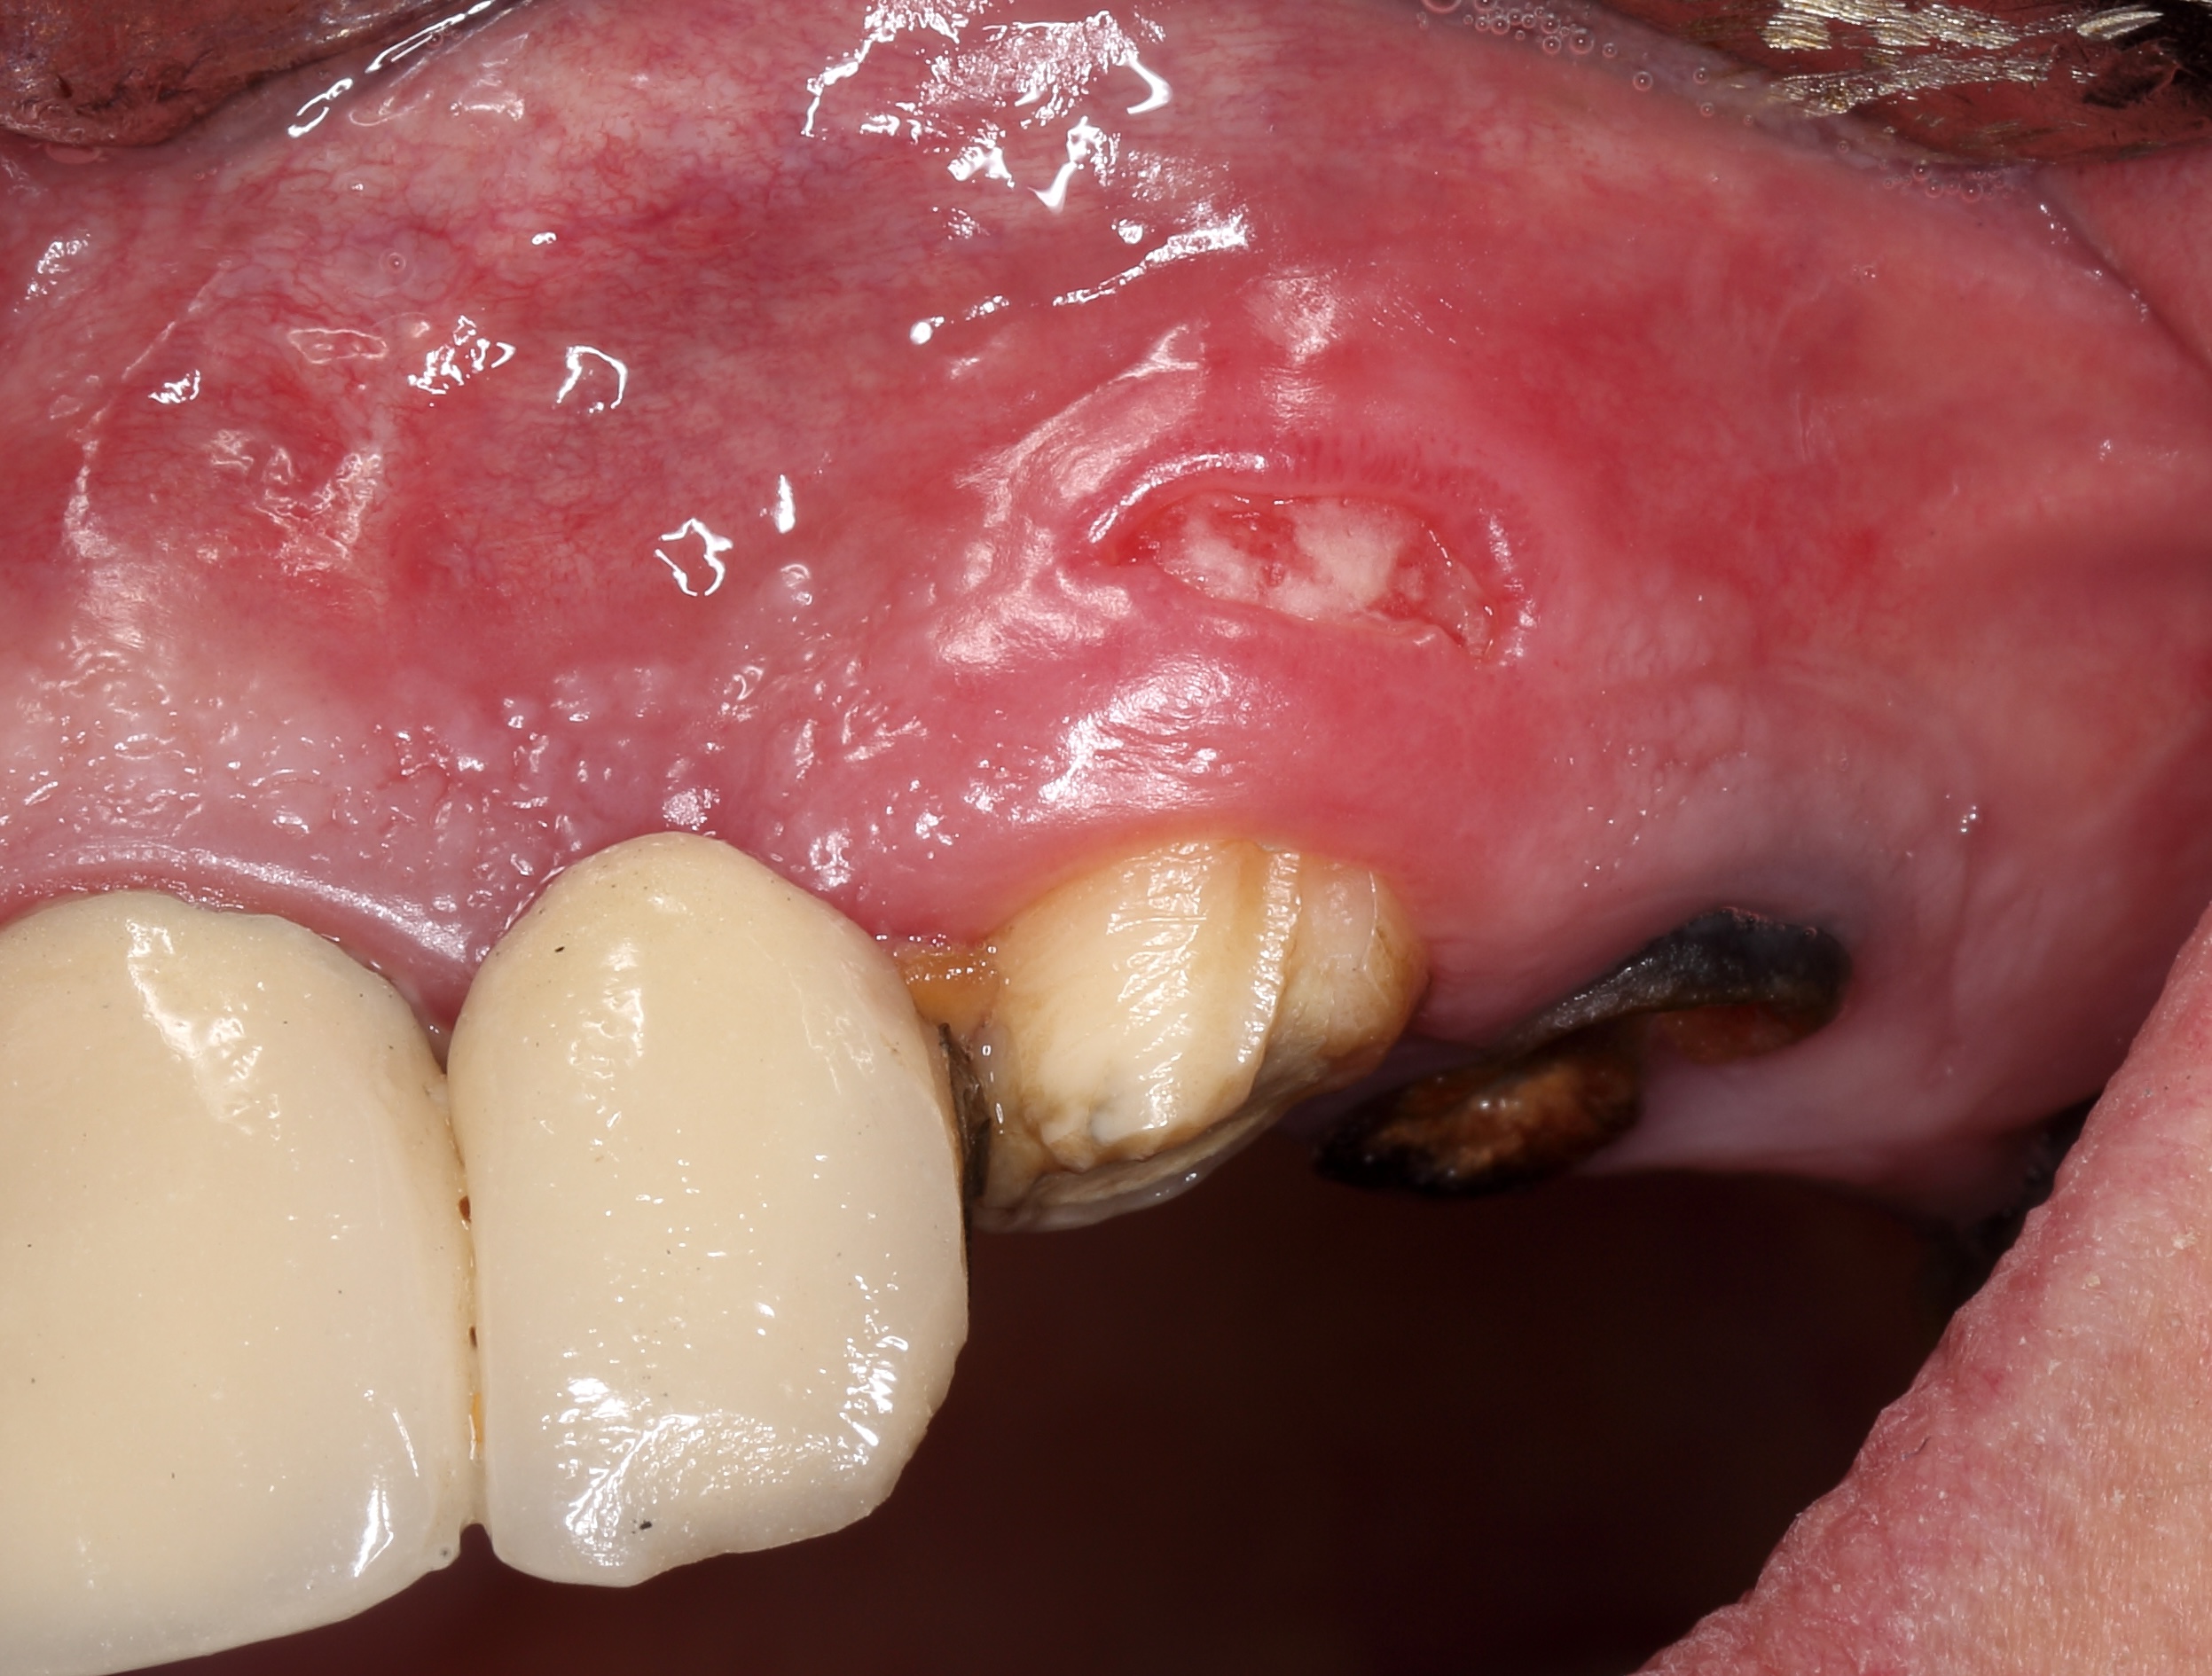

One of the postulates of “The golden rules of the flap design” reads, “The incision must never cross a bone defect. Incisions should be made away from the lesion if possible” [29]. More recent research also supports this view “The underlying apical lesion or surgical bony access must not extend to the flap margins” [16]. Using CBCT, the surgeon can accurately measure the size of the bone defect and plan the incision design so that the incision is at a distance from the bone defect (or the area where the osteotomy will be performed). If the surgery is not planned carefully and the incision passes through a bone defect, the risk of complications associated with healing increases significantly. There is the risk of postoperative infection [12]. These complications are sometimes observed (Fig 6).

One of the less well-described, rare and late complications of the Ochsenbein-Luebke incision is the occurrence of fenestrations in the soft tissues with baring bone. These fenestrations can be located both in the area of ​​the attached gingiva, which corresponds to the horizontal component of the incision (Fig 15), and on the transition of attached gingiva into the alveolar mucosa, which corresponds to the vertical component of the incision (Fig 16).

The development of soft tissue fenestrations with associated bone exposure is predominantly linked to a thin gingival biotype, suboptimal flap design, and inadequate wound closure.